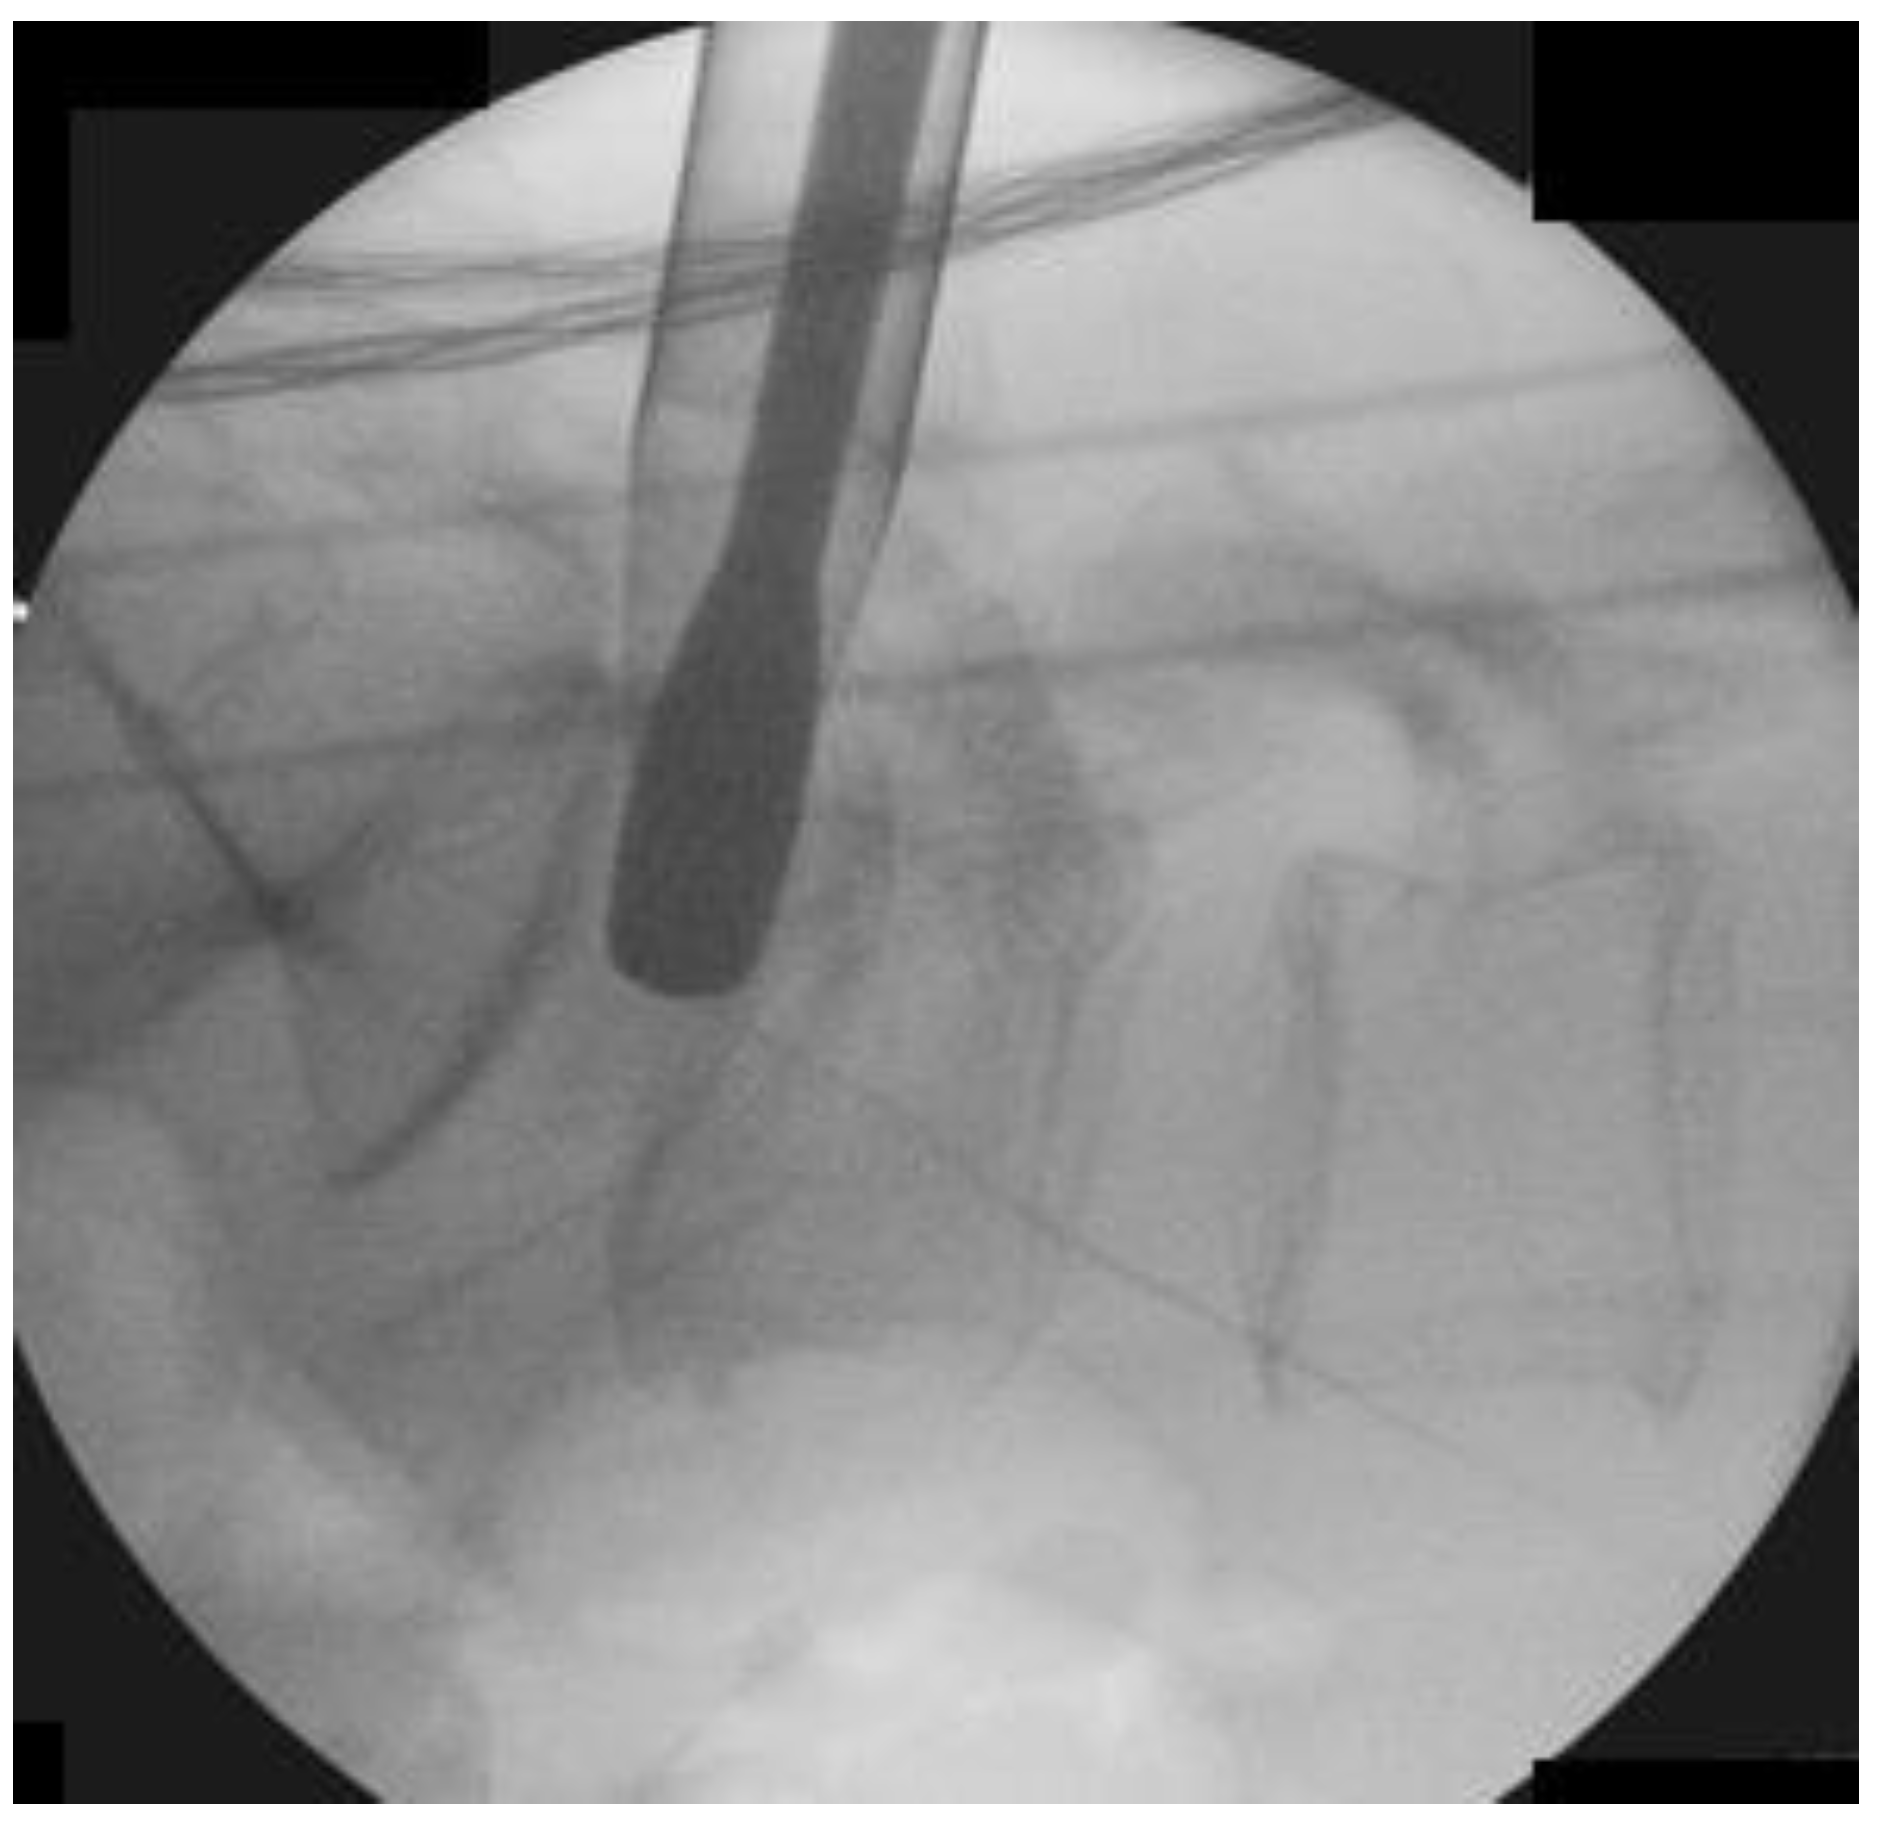

2.2.3. Insertion of Endoscope

Guidewire followed by serial dilators were placed through the skin incision and docked on the isthmus, which was followed by insertion of a 13.7 mm diameter beveled-tip working cannula. We performed an intraoperative anteroposterior and lateral view at this point of time to confirm the correct level of decompression. An endoscope of 15° viewing angle, outer diameter 10 mm, working channel diameter of 6 mm and working length 125 mm was inserted for the surgical procedure.